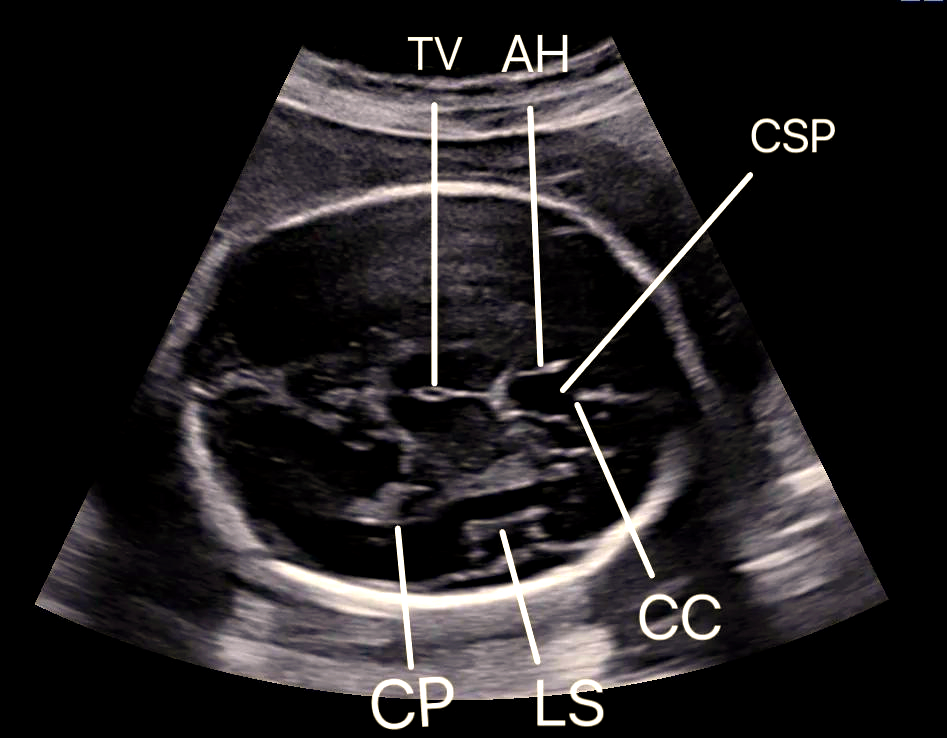

透明隔间腔图片

透明隔间腔,中间帆腔,vergae腔

透明隔间腔/vergae腔/中间帆腔

透明隔间腔 透明隔间腔是大脑内一个潜在的腔隙,位于两侧侧脑室之间

透明隔间腔是两侧侧脑室之间的间隔结构

胎儿透明隔腔的超声学习与了解